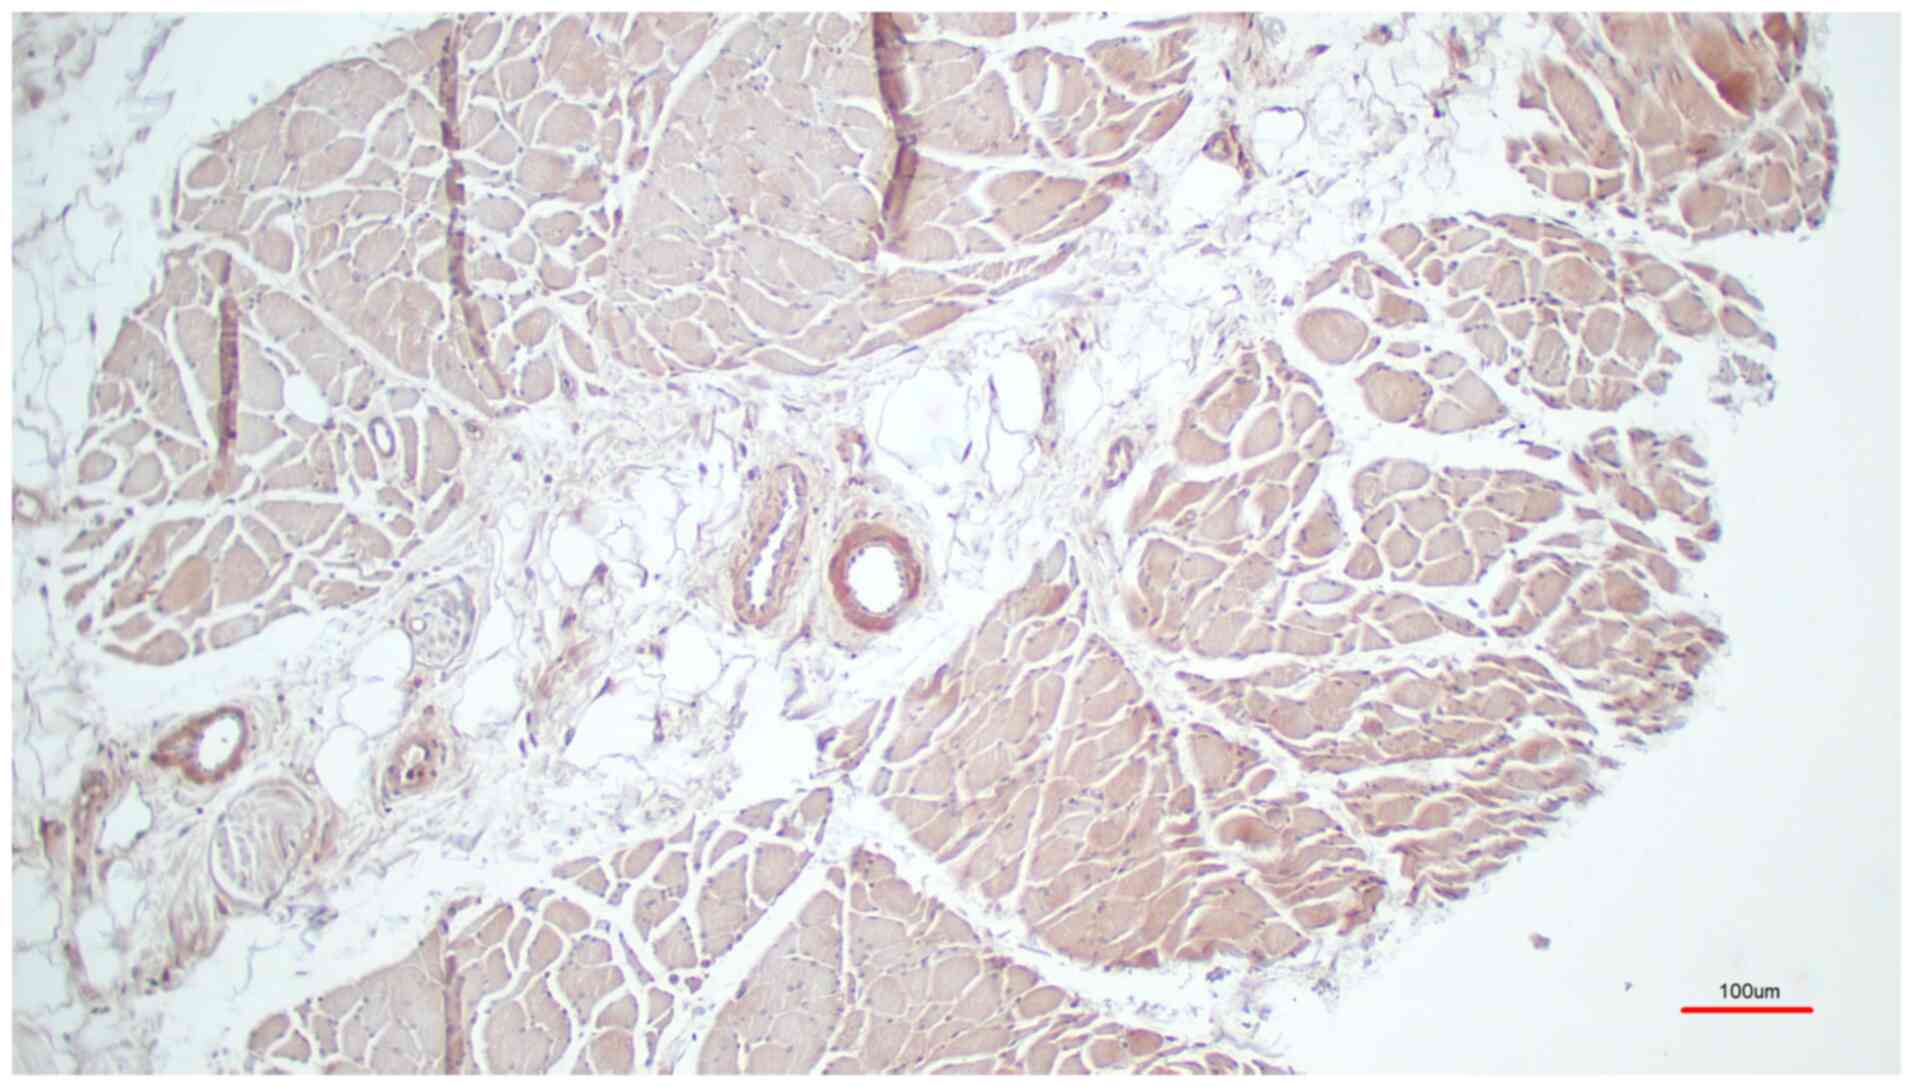

The results were evaluated microscopically and the samples were categorized according to staining intensity: Strong, weak and negative. From all the investigated samples, 19 samples exhibited strong staining and 2 samples exhibited weak staining. Nearly all (11 out of 12) samples that were preserved according to a protocol in a previous study by Janczyk et al (11) showed a strong immunohistochemical signal (Fig. 1, M. pectoralis major), while one sample was weakly stained. The four unfixed skeletal muscle samples consistently showed a strong immunohistochemical signal similar to the protocol by Janczyk et al (11). The five samples preserved using classical formaldehyde fixation showed a strong immunohistochemical signal in four cases (Fig. 2, M. triceps brachii), and a weak signal was detected in one case. Both controls, the normal rabbit serum control (Fig. 3) and the control with the peptide pre-incubation (Fig. 4), exhibited almost no immunohistochemically-stained structures. Another representative example of the presence of TRPC6 was revealed in a sample of M. deltoideus, which was obtained from an autopsy of a non-preserved cadaver (Table I, donor 8; Fig. 5, M. deltoideus). Collectively, representative examples of TRPC6 detection in human bodies are presented in M. deltoideus (Fig. 5), M. pectoralis major (Fig. 1) and M. triceps brachii (Fig. 2). An example of M. rectus femoris was lacking since it appeared identical to the other skeletal muscles. Skeletal muscles were presented from three different post mortem conditions: Non-preserved (Fig. 5), preserved according to the protocol by Janczyk et al (11) (Fig. 1) and preserved using classical formaldehyde fixation (Fig. 2).

Figure 1

Representative result of immunohistochemistry using the TRPC6 antibody of a sample of Musculus pectoralis major as preserved according to a protocol by Janczyk et al (11) (Table I, donor 3). All skeletal muscle fibers are indicated by brownish color whereas the fat cells are not labelled. TRPC6, transient receptor potential channel 6.

All skeletal muscle fibers were labelled with brownish color whereas the fat cells were not labelled (Fig. 5). In summary, TRPC6 was found in the fibers of all investigated skeletal muscles independent of whether the tissue was freshly obtained during autopsy or after preservation.